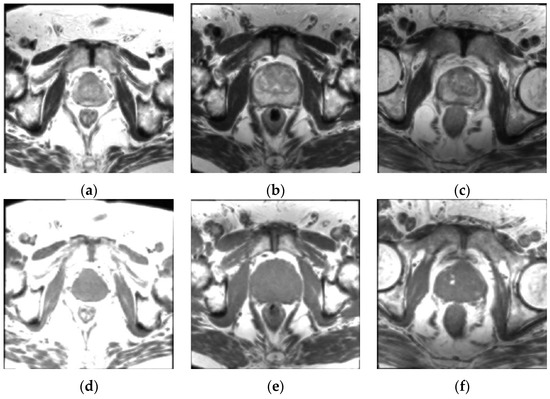

3.1. Patient Dataset Description

3.2.1. MR Image Co-Registration